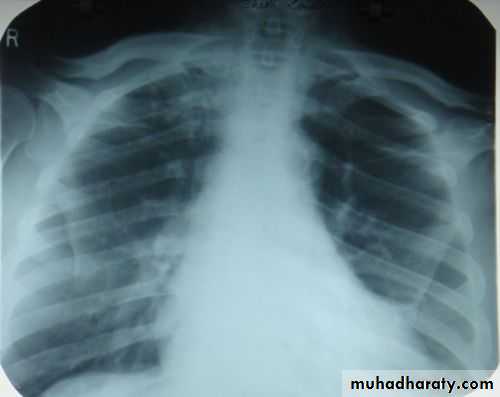

Tension pneumothorax.

On a posteroanterior chest x-ray (A), the left hemithorax is very dark or lucent because the left lung has collapsed completely (white arrows).

The tension pneumothorax can be identified because the mediastinal contents, including the heart, are shifted toward the right, and the left hemidiaphragm is flattened and depressed. A computed tomography scan done on a different patient with a tension pneumothorax (B) shows a completely collapsed right lung (arrows) and shift of the mediastinal contents to the left.

Tension Pneumothorax. Portable chest film in a 43-year-old woman with ARDS shows a large right pneumothorax with mediastinal shift and ipsilateral diaphragmatic depression, suggesting tension.

Air was evacuated under pressure during emergent placement of a right chest tube.